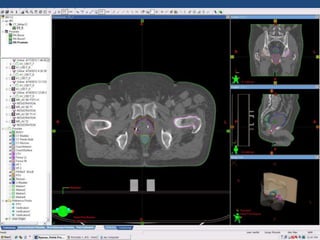

Prostate cancer is the second most common cancer globally, with varying incidence rates influenced by geography and lifestyle changes. In India, prostate cancer cases are rising due to urban migration and increased medical awareness, with current rates approaching those in Western countries. Treatment options vary by stage, including watchful waiting, surgery, radiation therapy, and hormonal treatment, each tailored to patient-specific factors.